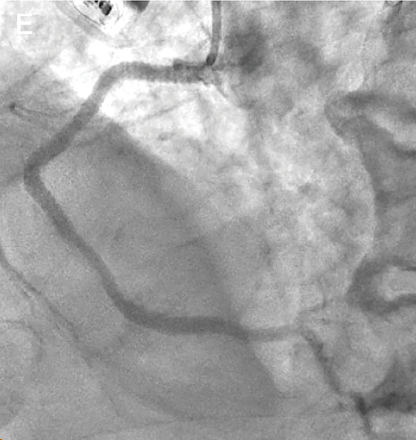

Quiz: Coronary IVL Tips and Tricks

This quiz is based on an interview with Andrew J.P. Klein, MD, FACC, FSVM, FSCAI. Click here to read "Coronary IVL Tips and Tricks."